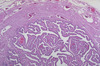

4A. Identify histological image A

Prostate

4B Identify histological image

Seminal vesicles